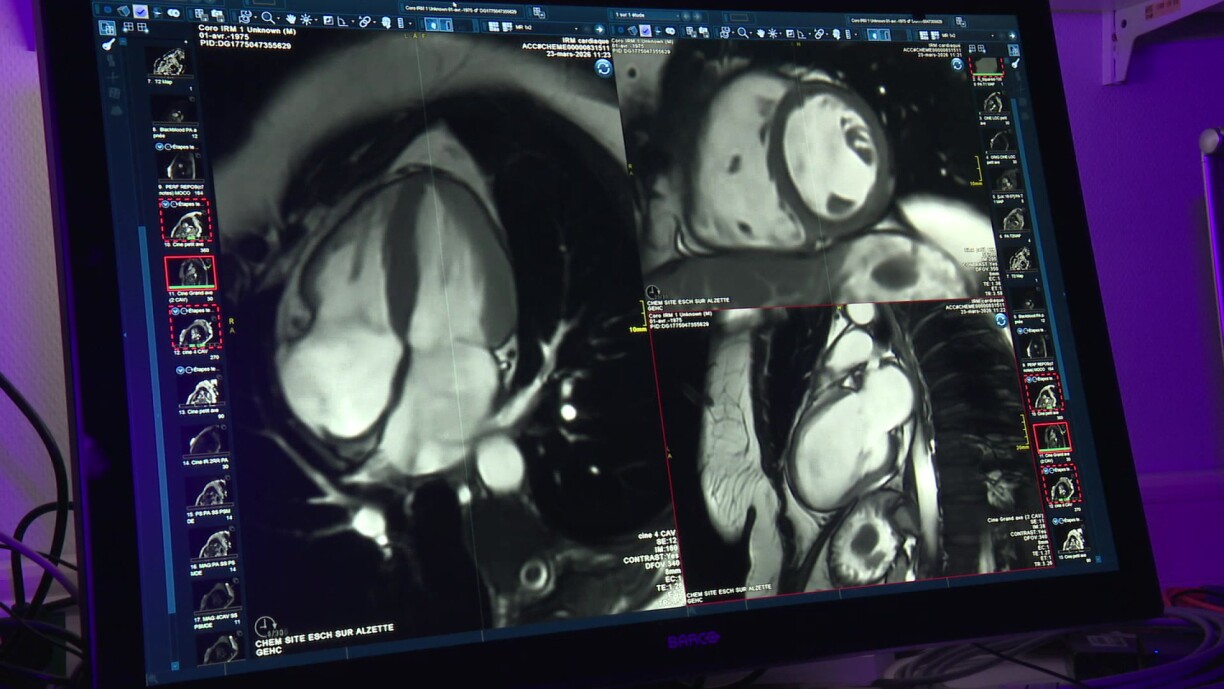

MRI, on the other hand, focuses on the heart’s function and the condition of the heart muscle, making it possible to detect issues such as myocarditis, which cannot be seen on a CT scan, according to Vanvinckenroye.

Last year, around 2,500 patients underwent CT scans and 300 had MRI examinations. The choice depends on what needs to be assessed, with CT scans generally taking less time than MRI.